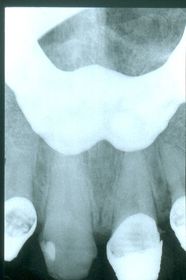

Objeto Interpuesto Causado cuando no se removió de la boca alguna prótesis removible antes de tomar la radiografía y aparece un objeto radiopaco.